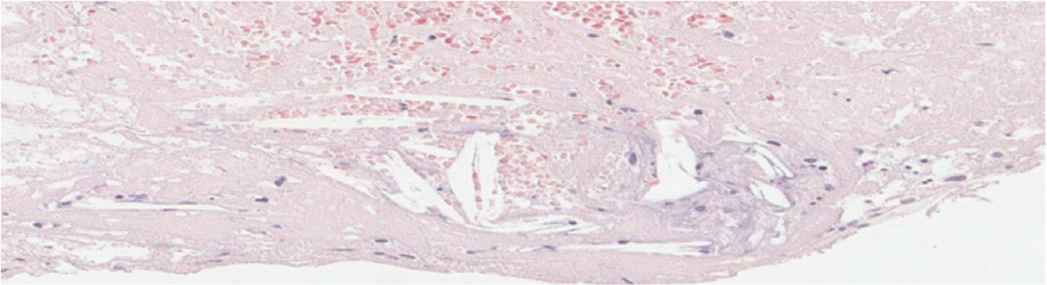

The participants consisted of men with an average age of 49.5 ± 11 years, of whom 20% had a history of coronary artery disease. The culprit vessels were right coronary artery, left anterior descending artery, and left circumflex in 48%, 44%, and 8%, respectively. There were two cardiogenic shock patients, and 44% had diabetes mellitus. The average D2B time was 127 ± 52 min. A no-reflow phenomenon was observed in 14 patients (56%). Upon histopathology study, we noticed that a predominant cleft of cholesterol was present, which may denote a high prevalence of dyslipidemia (Figure 1). The histopathology classification of thrombus based on age showed that 17 patients had recent thrombus (Figure 2), four patients had lytic thrombus (Figure 3), three patients had organized thrombus (Figure 4), two patients had no thrombus, and only patient had plaque components (Table 1). The histopathology data showed eight out of 25 patients had non-recent thrombus (32%), which implies the age of STEMI is more than 24 h despite the patients being clinically eligible for primary PCI (i.e., recorded onset of symptoms of <12 h).

Fresh thrombus (72.72%) showing intact Red Blood Cells (RBCs) and granulocytes amidst fibrin. Hematoxylin and Eosin (H&E), 40×.